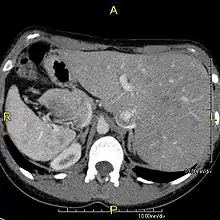

However, in some individuals with PCD, mutations thought to be in the gene coding for the key structural protein left-right dynein (lrd)[4] result in monocilia which do not rotate. There is therefore no flow generated in the node, Shh moves at random within it, and 50% of those affected develop situs inversus, which can occur with or without dextrocardia, where the laterality of the internal organs is the mirror-image of normal. Affected individuals therefore have Kartagener syndrome. This is not the case with some PCD-related genetic mutations: at least 6% of the PCD population have a condition called situs ambiguus or heterotaxy, where organ placement or development is neither typical (situs solitus) nor totally reversed (situs inversus totalis) but is a hybrid of the two.[6] Splenic abnormalities such as polysplenia, asplenia and complex congenital heart defects are more common in individuals with situs ambiguus and PCD, as they are in all individuals with situs ambiguus.[18]

When accompanied by the combination of situs inversus (reversal of the internal organs), chronic sinusitis, and bronchiectasis, it is known as Kartagener syndrome[3] (only 50% of primary ciliary dyskinesia cases include situs inversus).[11]